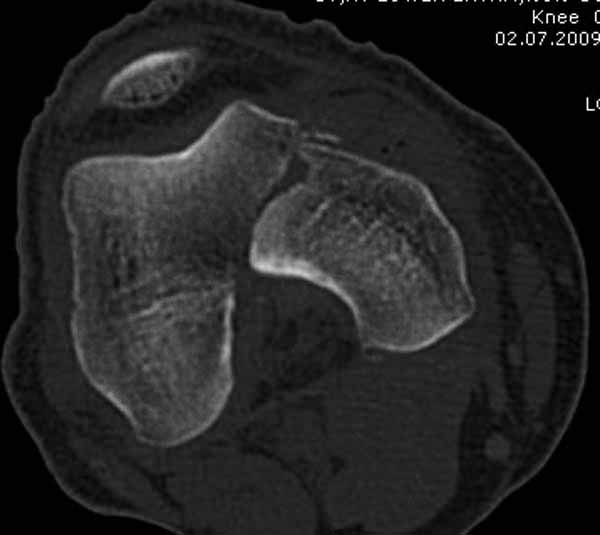

Однако в случае, представленном Константином Никитиным, не может быть применён ни ретроградный ни антеградный остеосинтез. Причина - нереально выполнить вышеуказанные необходимые требования, касающиеся дистальных блокирующих винтов. Из-за низкого перелома латерального мыщелка (перелом Hoffa) невозможно через него провести хотя бы 2 блокирующих винта, поскольку линия перелома мыщелка расположена либо на уровне верхушки межмыщелковой ямки либо незначительно проксимальнее. Поэтому авторам, с моей точки зрения, необходимо прислушаться к рекомендациям Джолдаса.

Рационально ориентироваться на качественный аспект - проблема или решается, или нет. Переломы типа 33C1 или C2 (то есть без фронтального раскалывания мыщелков, как на показанной Вами томограмме) при обычном качестве кости успешно можно фиксировать гвоздями с фронтальными винтами. Получается, их прочностных характеристик уже достаточно.

В приложении пример недавней операции, C3, открытая репозиция, фиксация мыщелков спицами и винтами, ретроградный синтез большеберцовым гвоздем 10,5 мм диаметром, винты 5 мм.